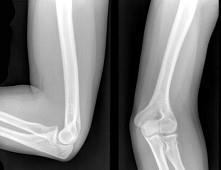

女,请根据其正常肘关节影像图像,判断其最可能的年龄 ( )A、37岁左右B、57岁左右C、27岁左右D、67岁左右E、17岁左右

问题 女,请根据其正常肘关节影像图像,判断其最可能的年龄 ( )

选项 A、37岁左右 B、57岁左右 C、27岁左右 D、67岁左右 E、17岁左右

答案 A